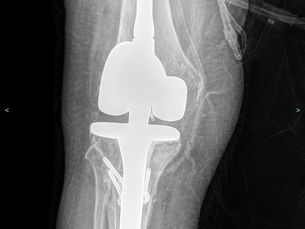

Revizyon Diz Protezi

Revizyon Diz Protezi uyguladığımız bir hastamız Daha önce diz protezi ameliyatı geçirdiniz, ancak zamanla ağrı yeniden başladı, diziniz şişiyor ya da yürümekte zorlanıyorsunuz. Doktorunuz "revizyon" sözcüğünü telaffuz etti ve kafanızda sorular birikmeye başladı. Bu yazıda revizyon diz ameliyatının ne anlama geldiğini, neden gerekebileceğini ve sürecin nasıl işlediğini sade bir dille anlatmaya çalışacağım. Revizyon Ameliyatı Ne Demek? Revizyon, daha önce yerleştirilen diz prot